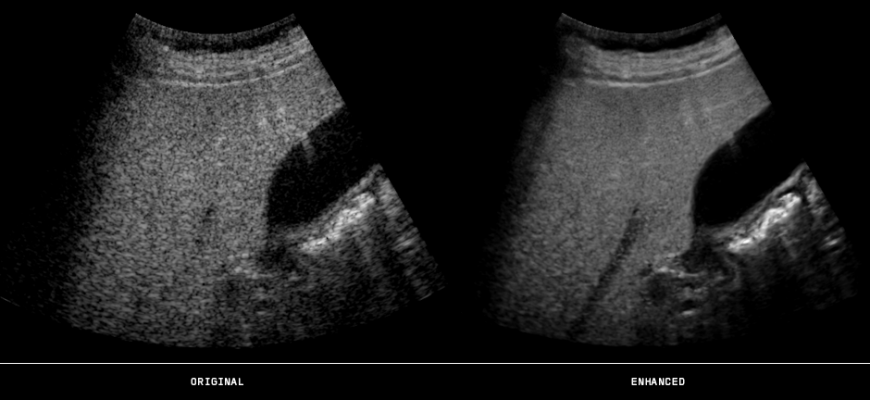

October 10, 2013 — At the Radiological Society of North America 2013 meeting (RSNA 2013), ContextVision will announce its latest additions to its U.S. PlusView Family, which will include four different packages for women’s health, general imaging, cardiovascular and point of care (POC). More anatomically correct images provide medical professionals diagnostic confidence for the most complex patient cases.

The PlusView software enhances ultrasound imaging with speckle reduction and edge-enhancement features. It also allows for deeper penetration, which could facilitate better ultrasound imaging of overweight patients